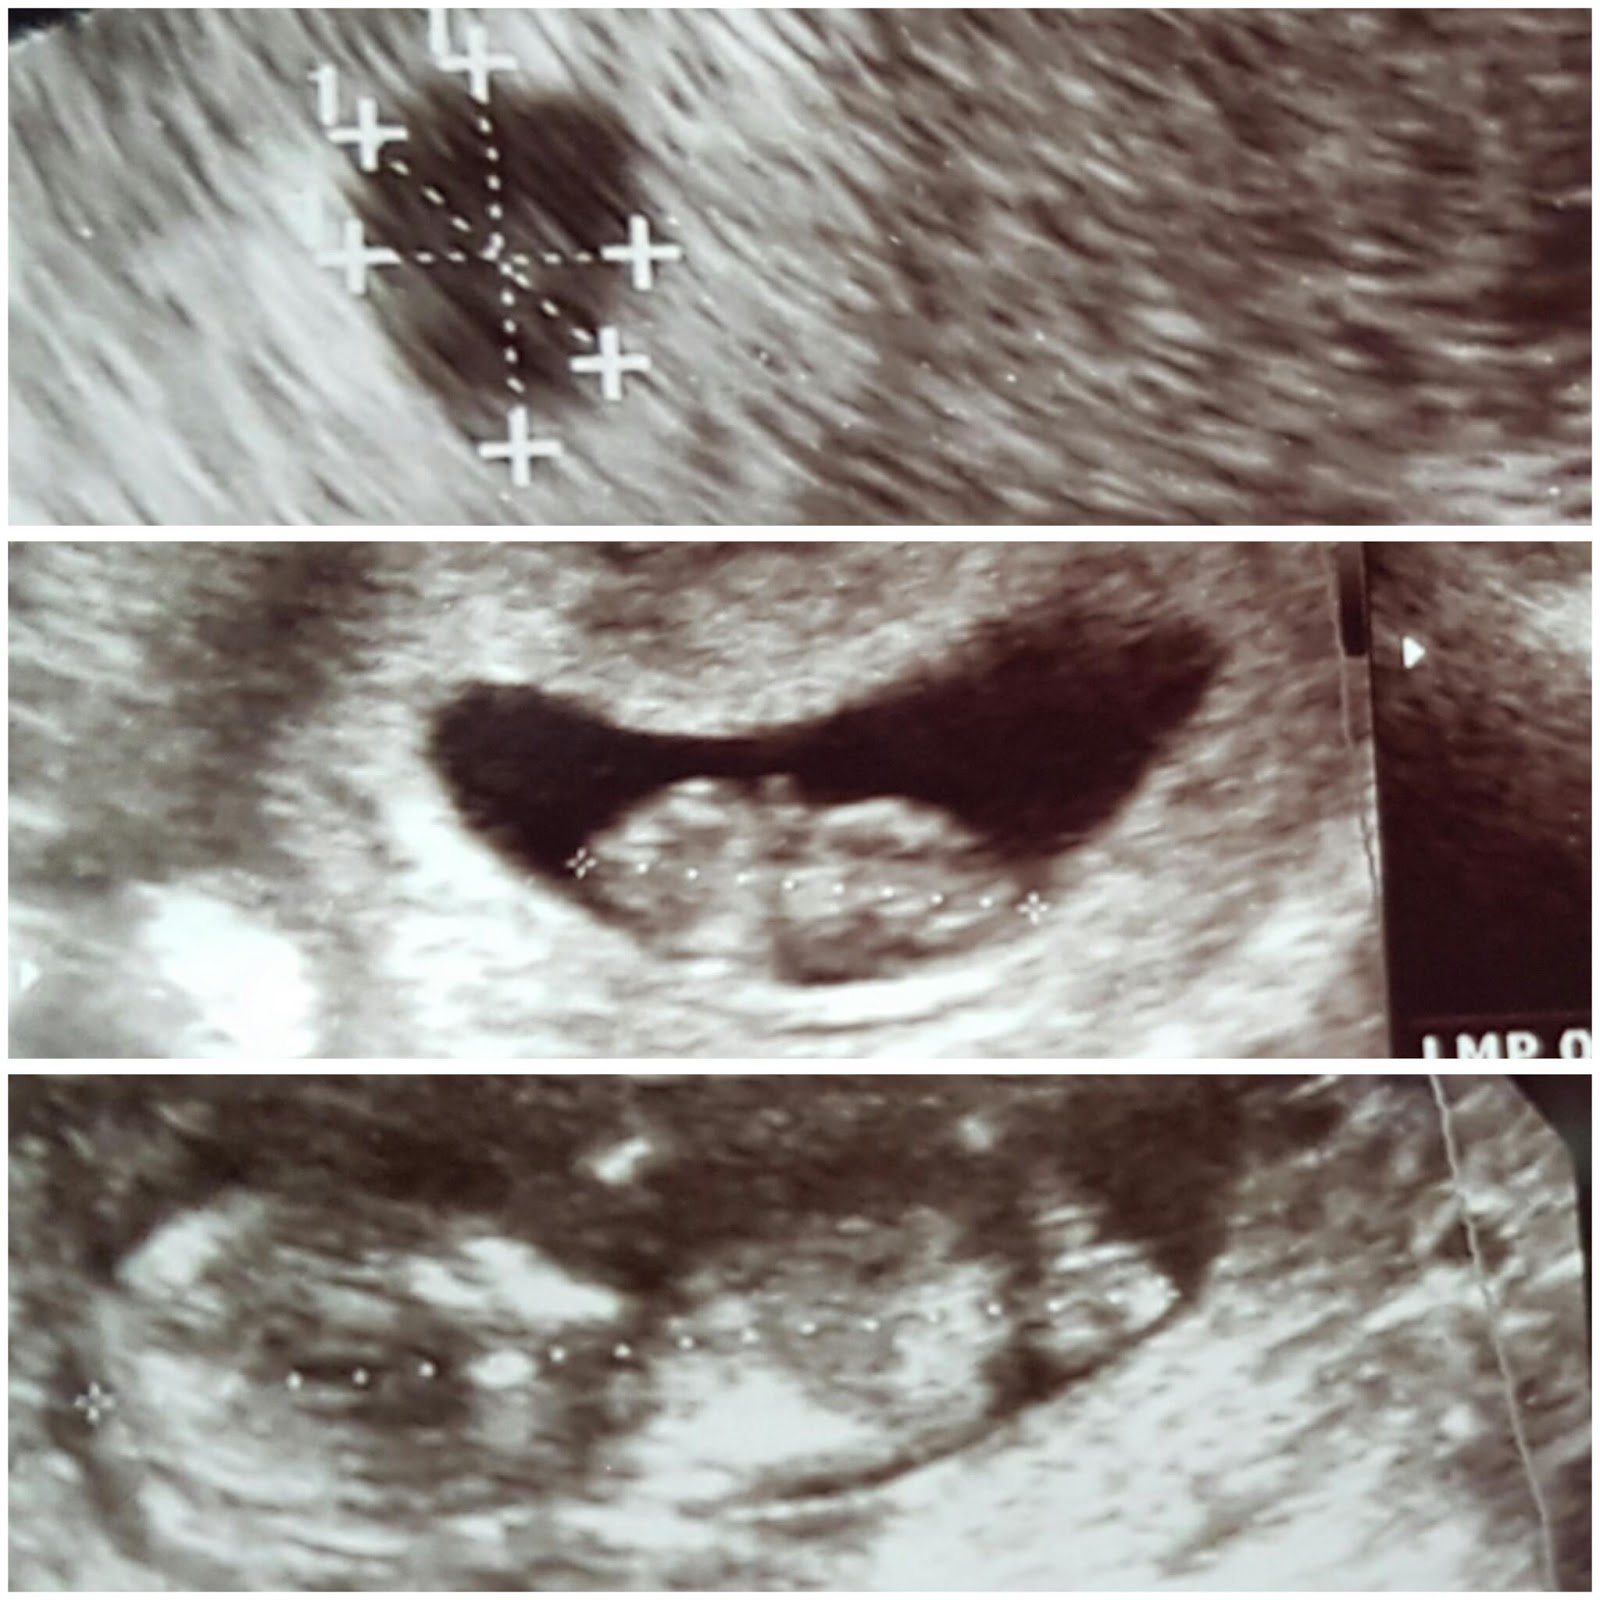

Akhirnya, malem itu juga saya ke dokter buat cek. Waktu itu karna kandungannya masih terlalu muda (dilihat dari tgl haid terakhir), jadi dicek dengan usg transvaginal. Usia kandungan saya waktu itu masih sekitar 5 weeks.

Pas di cek, dokter cuma bilang,

"Ibu, karna ini usia kandungannya masih terlalu muda, jadi saya ngga bisa jelasin banyak, karna memang masih sangat kecil, masih 1cm ukurannya. Saya cuma bisa bilang, Ibu positif hamil dan alhamdulillah hamilnya sudah di tempatnya. Kalau masalah calon janinnya kondisinya baik atau ngga, dll saya masih belum bisa jelasin, karna detak jantung juga belum bisa terdengar. Jadi nanti di cek lagi sebulan lagi ya"

Kurang lebih begitu penjelasan dokter. Fyi, jadi pentingnya kita cek ke dokter ya karna ini, kita ngga tau kondisi calon janin kita di dalam gimana. Karna ada juga yg katanya hamil di luar kandungan.